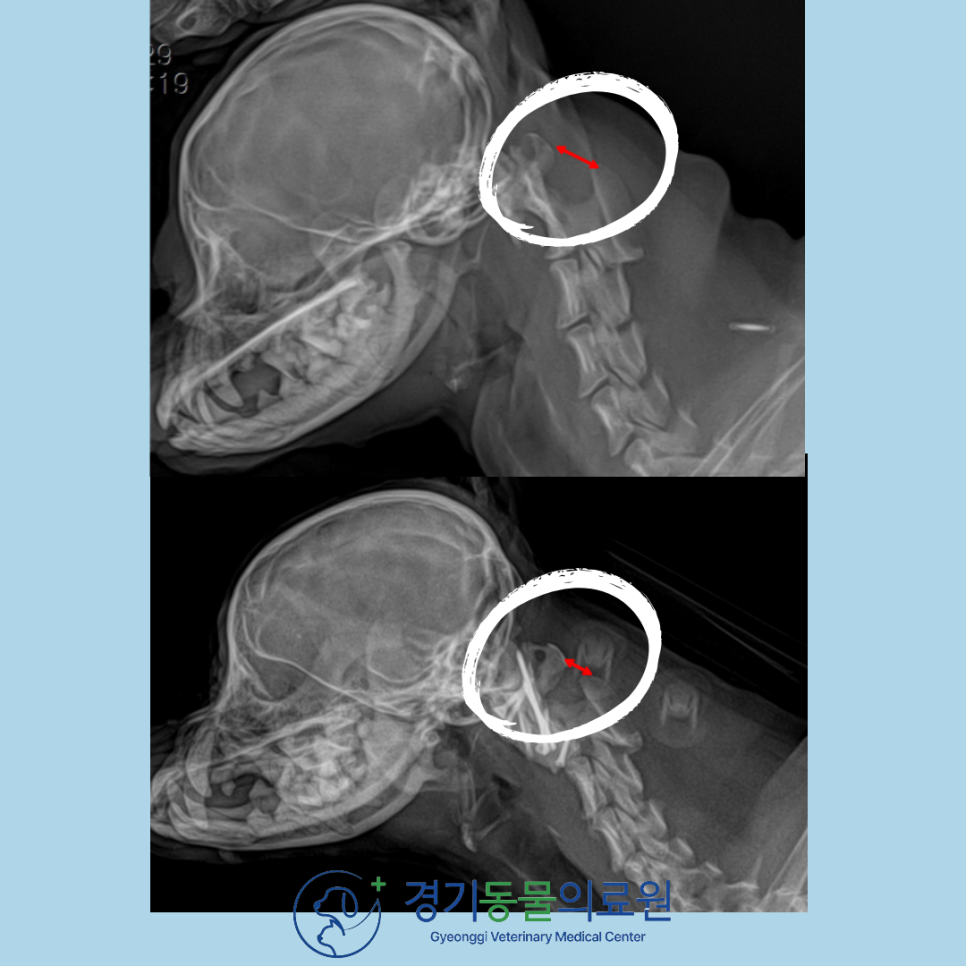

방사선 검사 상에서 경추1번과 경추2번 사이의 불안정성이 뚜렷하게 확인되었고,

정밀한 평가를 위해 CT촬영까지 진행하였습니다.

수술은 계획했던 대로 잘 진행되었고, 수술 후(아래) 경추1번과 경추2번 사이의 거리가 정상적으로 환납되었음을 확인하였습니다(4mm이내).